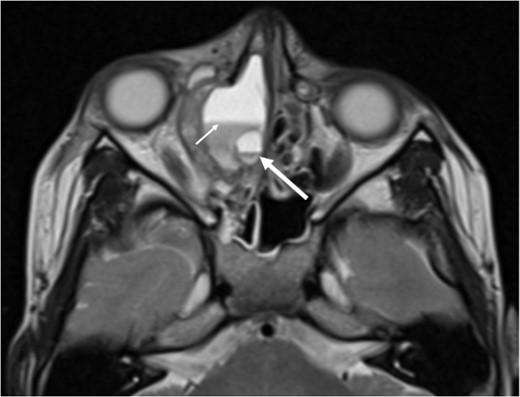

Axial T1 post-contrast sequence with fat suppression demonstrating peripheral enhancement (white arrows) but no internal or solid enhancing components to suggest that this is a secondary ABC.